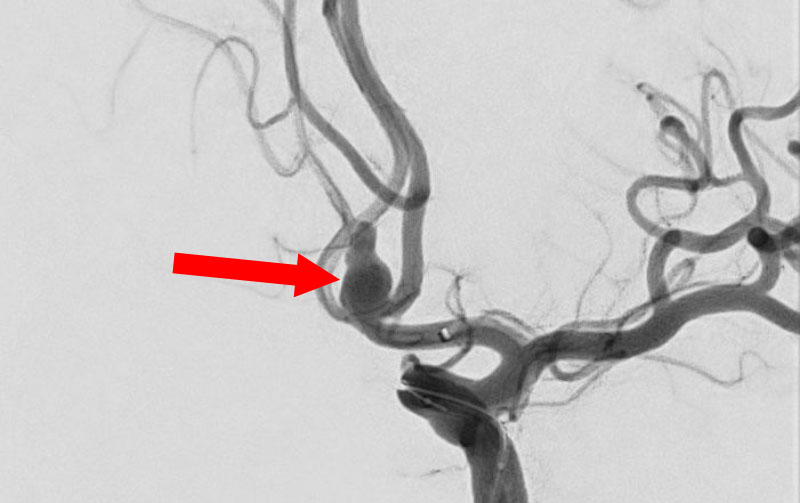

くも膜下出血

左中大脳動脈瘤破裂

40代

救急外来

No.1596 手術前

No.1596 手術中

No.1596 手術後